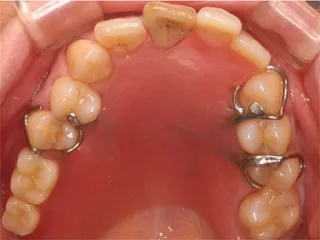

保険の義歯 保険の義歯

保険義歯は鉤が金属でプラスチック製なので割れないように厚く大きく作ります

同じケースで 軟性義歯「バルプラスト」に切り替えると鉤がないので審美性に優れ装着感が楽になると好評です